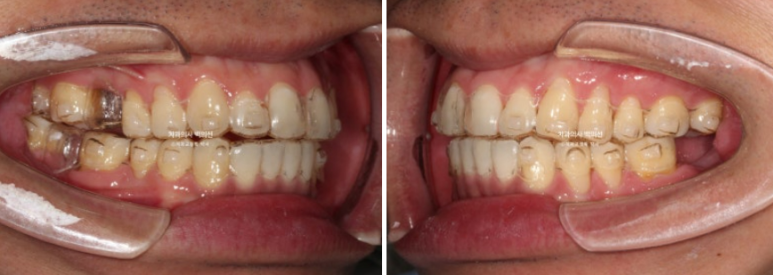

24.05~24.11

쓰러진 큰어금니를 세워 좁아진 임플란트 공간을 2mm 가량 더 확보했습니다.

배열도 개선이 많이 되었습니다.

24.05~25.03